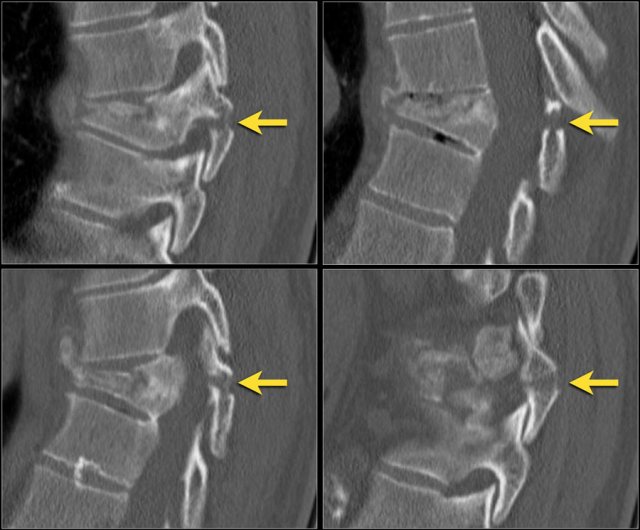

Sagittal fracture of vertebral body and posterior element

A sagittal fracture of the vertebral body and a sagittal posterior element fracture is seen in respectively 90% and 85% of cases of burst fracture cases.

Here are four examples.

In the Denis classification this would be a three column fracture -anterior/middle/posterior - indicating a very unstable fracture.

In the TLICS classification however this is a burst fracture, i.e. 2 points for morphology.

The treatment will depend on the PLC integrity and the neurological status.